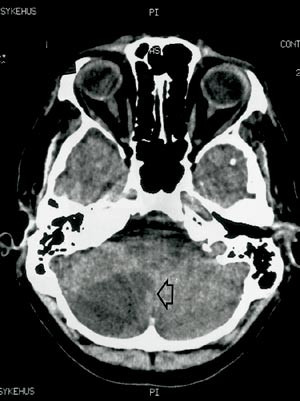

Han ble akutt syk med hodepine, svimmelhet, kvalme og brekninger. Symptomene gikk helt tilbake i løpet av få timer, med unntak av hodepinen, som likevel avtok etter hvert. Ved innleggelse i lokalsykehus samme kveld fant man ingen nevrologiske utfall. Cerebral CT viste imidlertid utvikling av et stort høyresidig lillehjerneinfarkt (fig 1). Det tilkom ikke trykksymptomer. Han ble overflyttet nevrologisk avdeling for videre utredning.